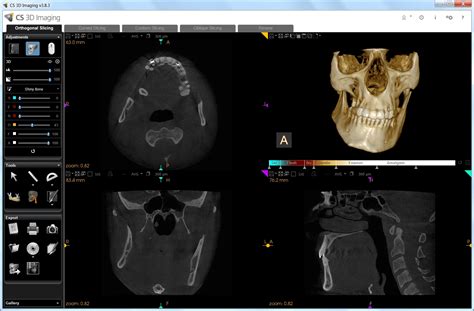

Un paciente de 58 años fue remitido al Departamento de Prostodoncia para evaluación de un posible tratamiento protésico. Durante la evaluación radiográfica de rutina, se identificó incidentalmente una radiolucidez interradicular asintomática en las regiones 11 y 21. La tomografía volumétrica digital reveló una masa circunscrita interradicular palatina que comunicaba con la fosa nasal izquierda, lo que llevó al diagnóstico de sospecha de un agujero incisivo ensanchado.

El caso presentado destaca la importancia de considerar las variantes anatómicas normales en el diagnóstico radiográfico. El agujero incisivo ensanchado es una variante anatómica normal que carece de significado patológico. En imágenes radiológicas bidimensionales, la sobreproyección de la espina nasal anterior o del tabique nasal puede generar la impresión de una radiolucidez en forma de corazón, lo que sugiere erróneamente un quiste nasopalatino.

Ante la detección de una masa radiotransparente en una radiografía panorámica, se recomienda obtener una segunda radiografía en una proyección distinta. En procesos más extensos, se recomienda recurrir a exámenes radiológicos más detallados, como una tomografía volumétrica digital dental, que proporciona una imagen tridimensional de las estructuras anatómicas.

En pacientes asintomáticos, se debe considerar siempre la posibilidad de que la radiolucidez sea solo la expresión de un agujero incisivo de grandes dimensiones. Los estudios anatómicos han documentado variantes anatómicas normales de hasta 10 mm, con tamaños de 6 a 7 mm no siendo excepcionales.

En el caso presentado, se descartó un proceso patológico, dado que la radiolucidez resultó ser una variante anatómica normal del agujero incisivo. Por ello, se prescindió de tomar alguna medida terapéutica.